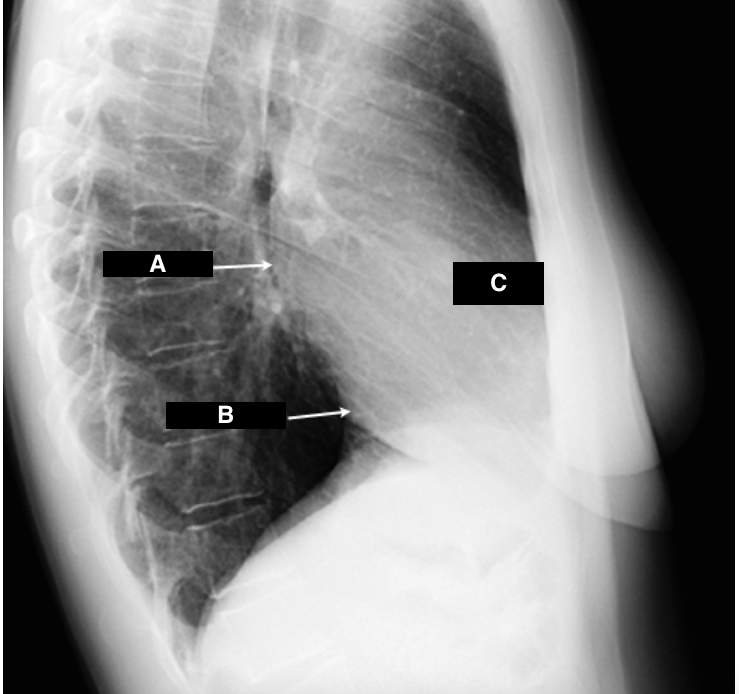

Identify A, B, C.

A

A - Left Atrium

B - Left Ventricle

C - Right Ventricle